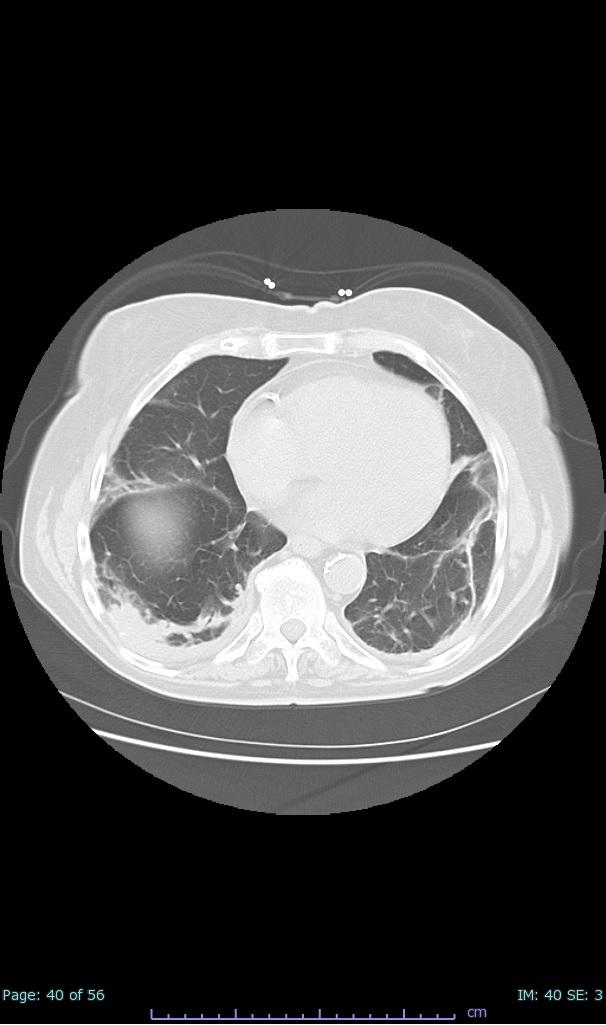

- 100% subpleural involvement, 33% + centrolobular involvement

- 40% even apical/basilar, 27% basilar dom, 5% mid dom. 1/17

- 66% had some + CXR finding I could correlate to a CT finding

- 66% had documented exposure, rest I couldn't find either way